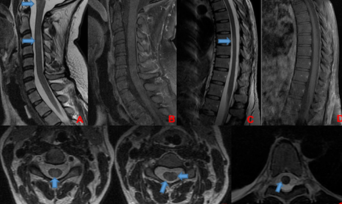

Postpartum Myelitis Following Dengue-Related Limbic…